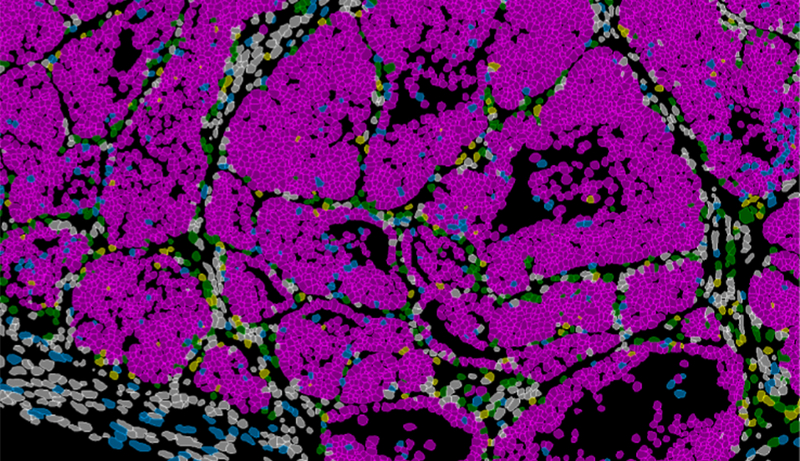

A partir de models en ratolí i de dades de pacients amb càncer de mama, el laboratori de Plasticitat Cel·lular en Desenrotllament i Malaltia, dirigit per Ángela Nieto, va descriure una població concreta de cèl·lules situada en la vora invasiva del tumor. Estes cèl·lules són capaces tant d’invadir teixits veïns com de dividir-se activament o, en altres circumstàncies, d’entrar en letargia durant llargs períodes.

Per a arribar a estes conclusions, els investigadors van combinar diferents enfocaments experimentals. Van utilitzar models genètics en ratolí, anàlisi de cèl·lula única i estudis de cromatina, a més de tècniques que permeten observar directament, en el propi teixit tumoral, com s’organitzen i es comporten les cèl·lules. Esta estratègia integrada els va permetre seguir amb detall la transició entre cèl·lules en repòs i cèl·lules amb potencial metastásico.